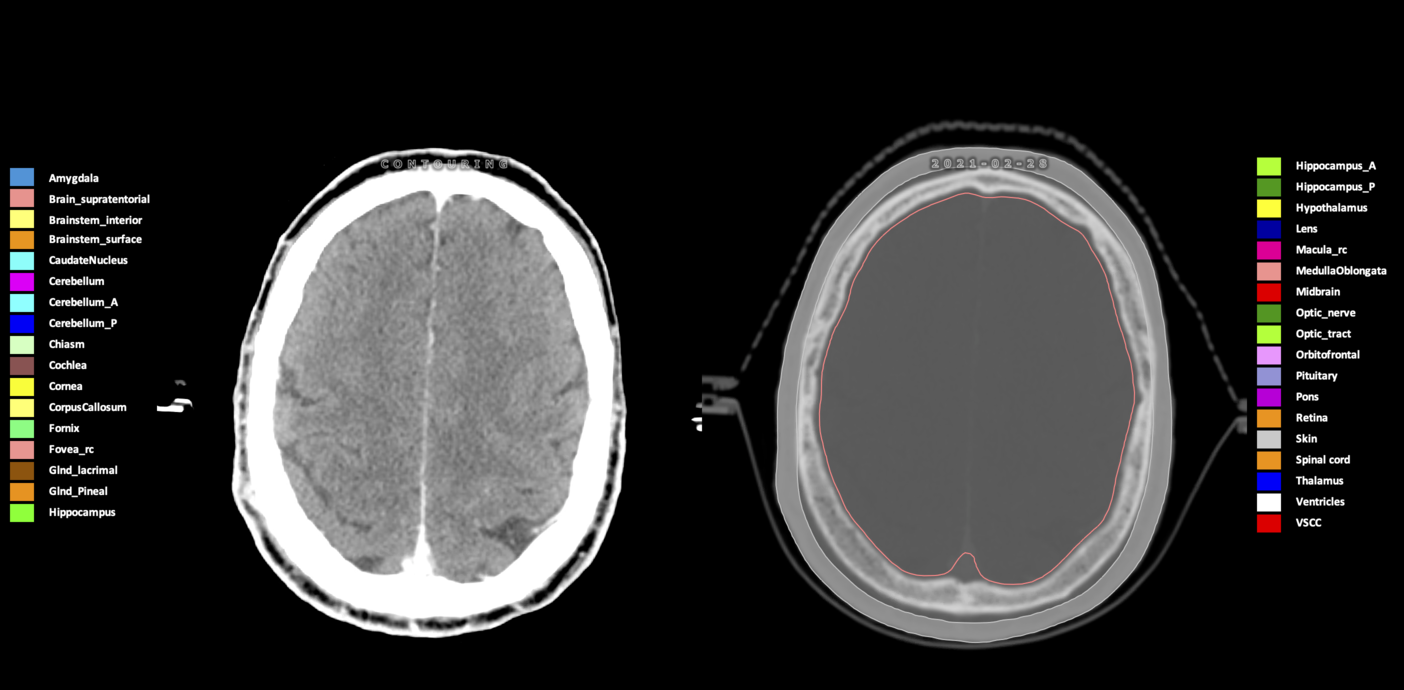

Included are all OARs known to be relevant for radiation-induced toxicity in neuro-oncology: brain, brainstem (midbrain, pons, medulla oblongata), chiasm, cerebellum (anterior & posterior), cochlea, cornea, hippocampus (anterior & posterior), hypothalamus, lens, lacrimal gland, optic nerve, pituitary, skin, and vestibular & semicircular canals. To further facilitate research on cognition, vision and radiological changes after irradiation of the brain, potential clinically-relevant OARs are included: amygdala, caudate nucleus, cerebellum (anterior & posterior), corpus callosum, fornix, macula, optic tract, orbitofrontal cortex, periventricular space (PVS), pineal gland, and thalamus.

Three-dimensional delineation of the 25 consensus OARs for neuro-oncology are shown on CT (WW/WL 120/40, 3000/600), 3T MR images, (T1Gd, T2FLAIR 1mm) and 7T MR (MP2RAGE 0.7 mm). All are presented in transversal, sagittal and coronal view.